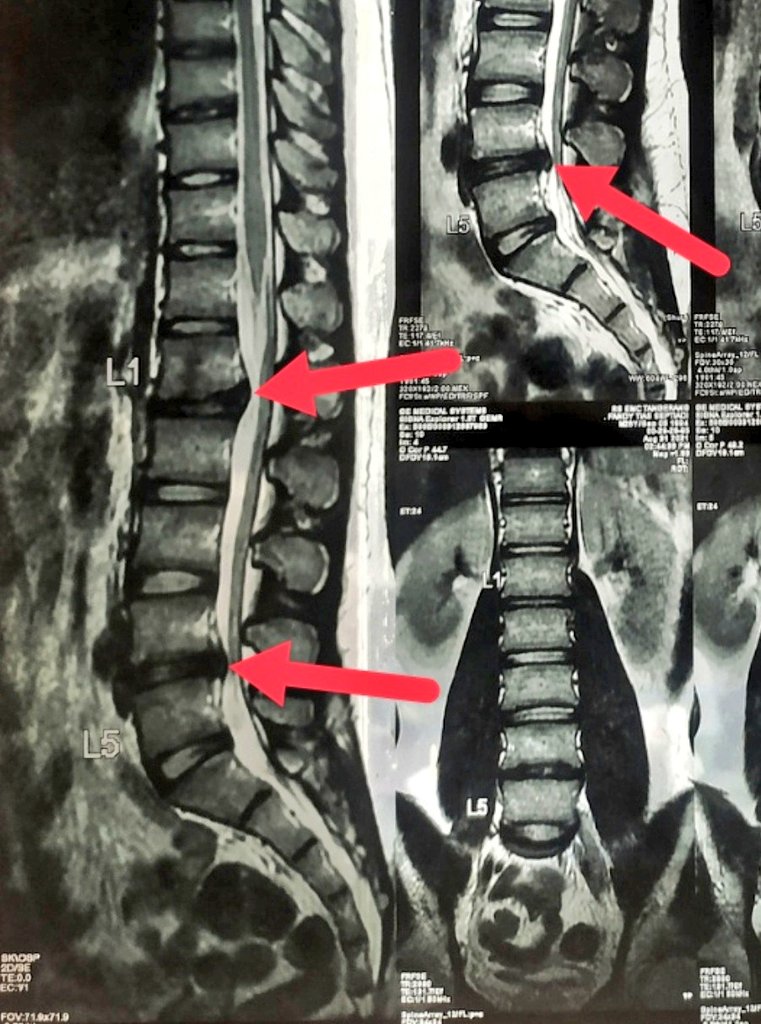

Pun sama dgn yg gw alami. Gw cedera dibagian Lumbar (Pinggang) L1-L2 & L4-L5. Alignment tulang gw masih bagus, lurus. Tapi tetep si sarafnya keteken sama bantalan yg keluar. Saraf kaki kanan yg kena. Alhamdulillah gk smpe lumpuh. Cuma emg sakit luar biasa menjalar ke kaki.

13 desember 2021. Gw oprasi Decompression. Bantalan yg neken saraf diambil sebagian sehingga mengurangi tekanan pada saraf.